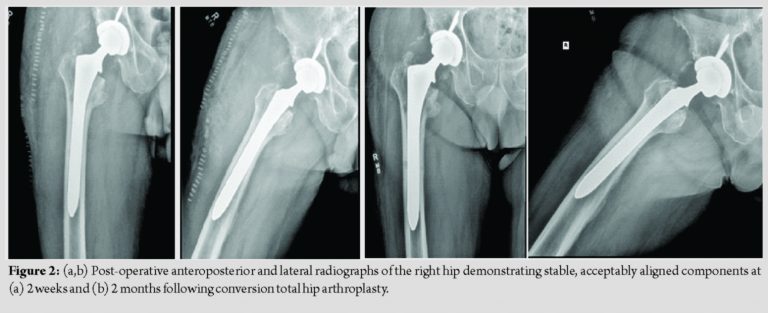

The patient was placed on the pre-established protocol during and after the surgery. He was cleared by physical therapy on post-operative day 1, and plans were made for discharge to home with a rolling walker. The patient was observed closely for signs of bleeding, and he remained asymptomatic throughout his hospital course. The patient’s hemoglobin and hematocrit did decrease to 8.0 g/dL and 24.6% before stabilizing, and no transfusion was necessary. Ultimately, the patient was discharged to home in stable condition on post-operative day 3, shortly after finishing nine doses of IV TXA per the previously established protocol. Follow-up was obtained at 2 weeks, 2 months, 5 months, and 10 months, with post-operative radiographs obtained at 2 weeks and 2 months (Fig. 2). The patient continued to progress to weight-bearing as tolerated without issue. Follow-up X-rays demonstrated stable and well-aligned components. His pre-operative pain improved dramatically. Despite some mild stiffness and a small leg length discrepancy, the patient’s overall clinical status improved significantly and he remains very satisfied with the outcome of his surgery. He did not have any bleeding-related complications throughout his perioperative course. At 10 months, the patient reported no complications, and he noted that he was back to full activity including hiking and snowshoeing without pain or other noticeable symptoms.